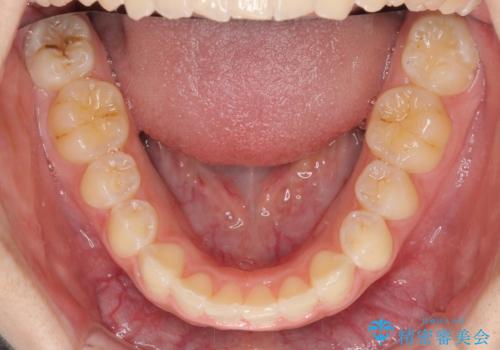

前歯のデコボコを治したい インビザライン矯正治療

- 前歯のデコボコ気になるとのことで来院された患者様です。

下顎骨が上顎骨に対して右側にシフトしており、さらに下顎が後方に位置しているため、非常に強い咬合力で食いしばっている状態でした。

上下顎ともに歯列全体の後方移動とIPR(歯と歯の間を削る)によってデコボコが解消するように設計し、インビザラインにより治療を行うこととしました。

強い咬合力による臼歯部の噛みにくさと、それに伴う歯の移動の鈍さに悩まされ、非常に長い期間を要することとなりました。

上下正中位置は、治療開始時よりは改善したものの、ここが限界であろうというところでのゴールとなりました。

下顎前歯の大半が隠れている状態ですが、左右への歯ぎしりはスムーズに行うことができ、就寝時には後戻り防止も兼ねて、食いしばり対策としてマウスピースの使用を継続するようお願いしております。